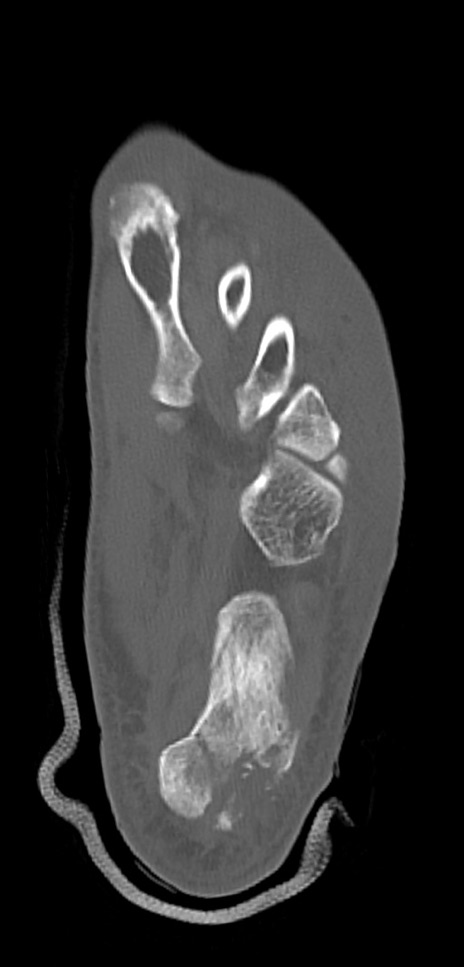

症例37 左足関節CT(横断像)

左足関節CT